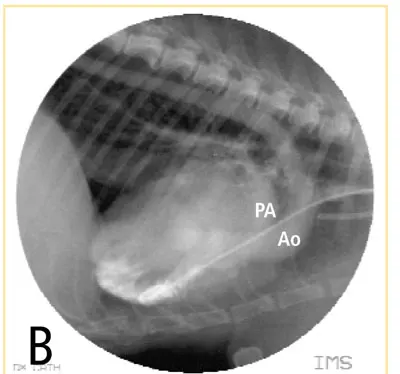

Central cyanosis occurs when the circulating blood has more than 5 g/dL of hemoglobin desaturated of oxygen. This can be seen in animals with clinically significant pulmonary disease and hypoxemia or with right-to-left cardiovascular shunts, such as a reverse patent ductus arteriosus and tetralogy of Fallot (Figure B). This right ventricular angiogram demonstrates blood flow from the right ventricle into the aorta (Ao) and pulmonary artery (PA) in a cat with tetralogy of Fallot.